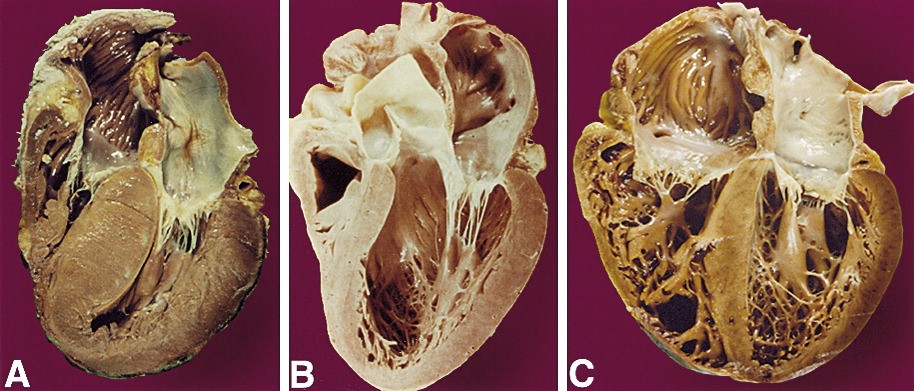

سه شکل شایع کاردیومیوپاتی٬ کاردیومیوپاتی گشادشده که شایعترین شکل کاردیومیوپاتی است، کاردیومیوپاتی هیپرتروفیک یا رشد دیواره و ضخیمشدن عضله قلب و نیز کاردیومیوپاتی محدودکننده (Restrictive) ( کاهش انعطافپذیری عضلات قلب) میباشد.

کاردیومیوپاتی هیپرتروفیک (HCM)

کاردیومیوپاتی گشادشده (DCM)

کاردیومیوپاتی محدودکننده (RCM)